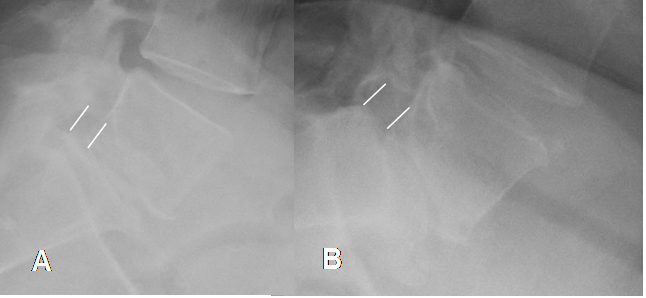

Fig 76. Inestabilidad.

A: Rx lateral neutra y B: Rx lateral en flexión. Anterolistesis GI de L5, sobre S1, que aumenta en la proyección de flexión e indica inestabilidad.